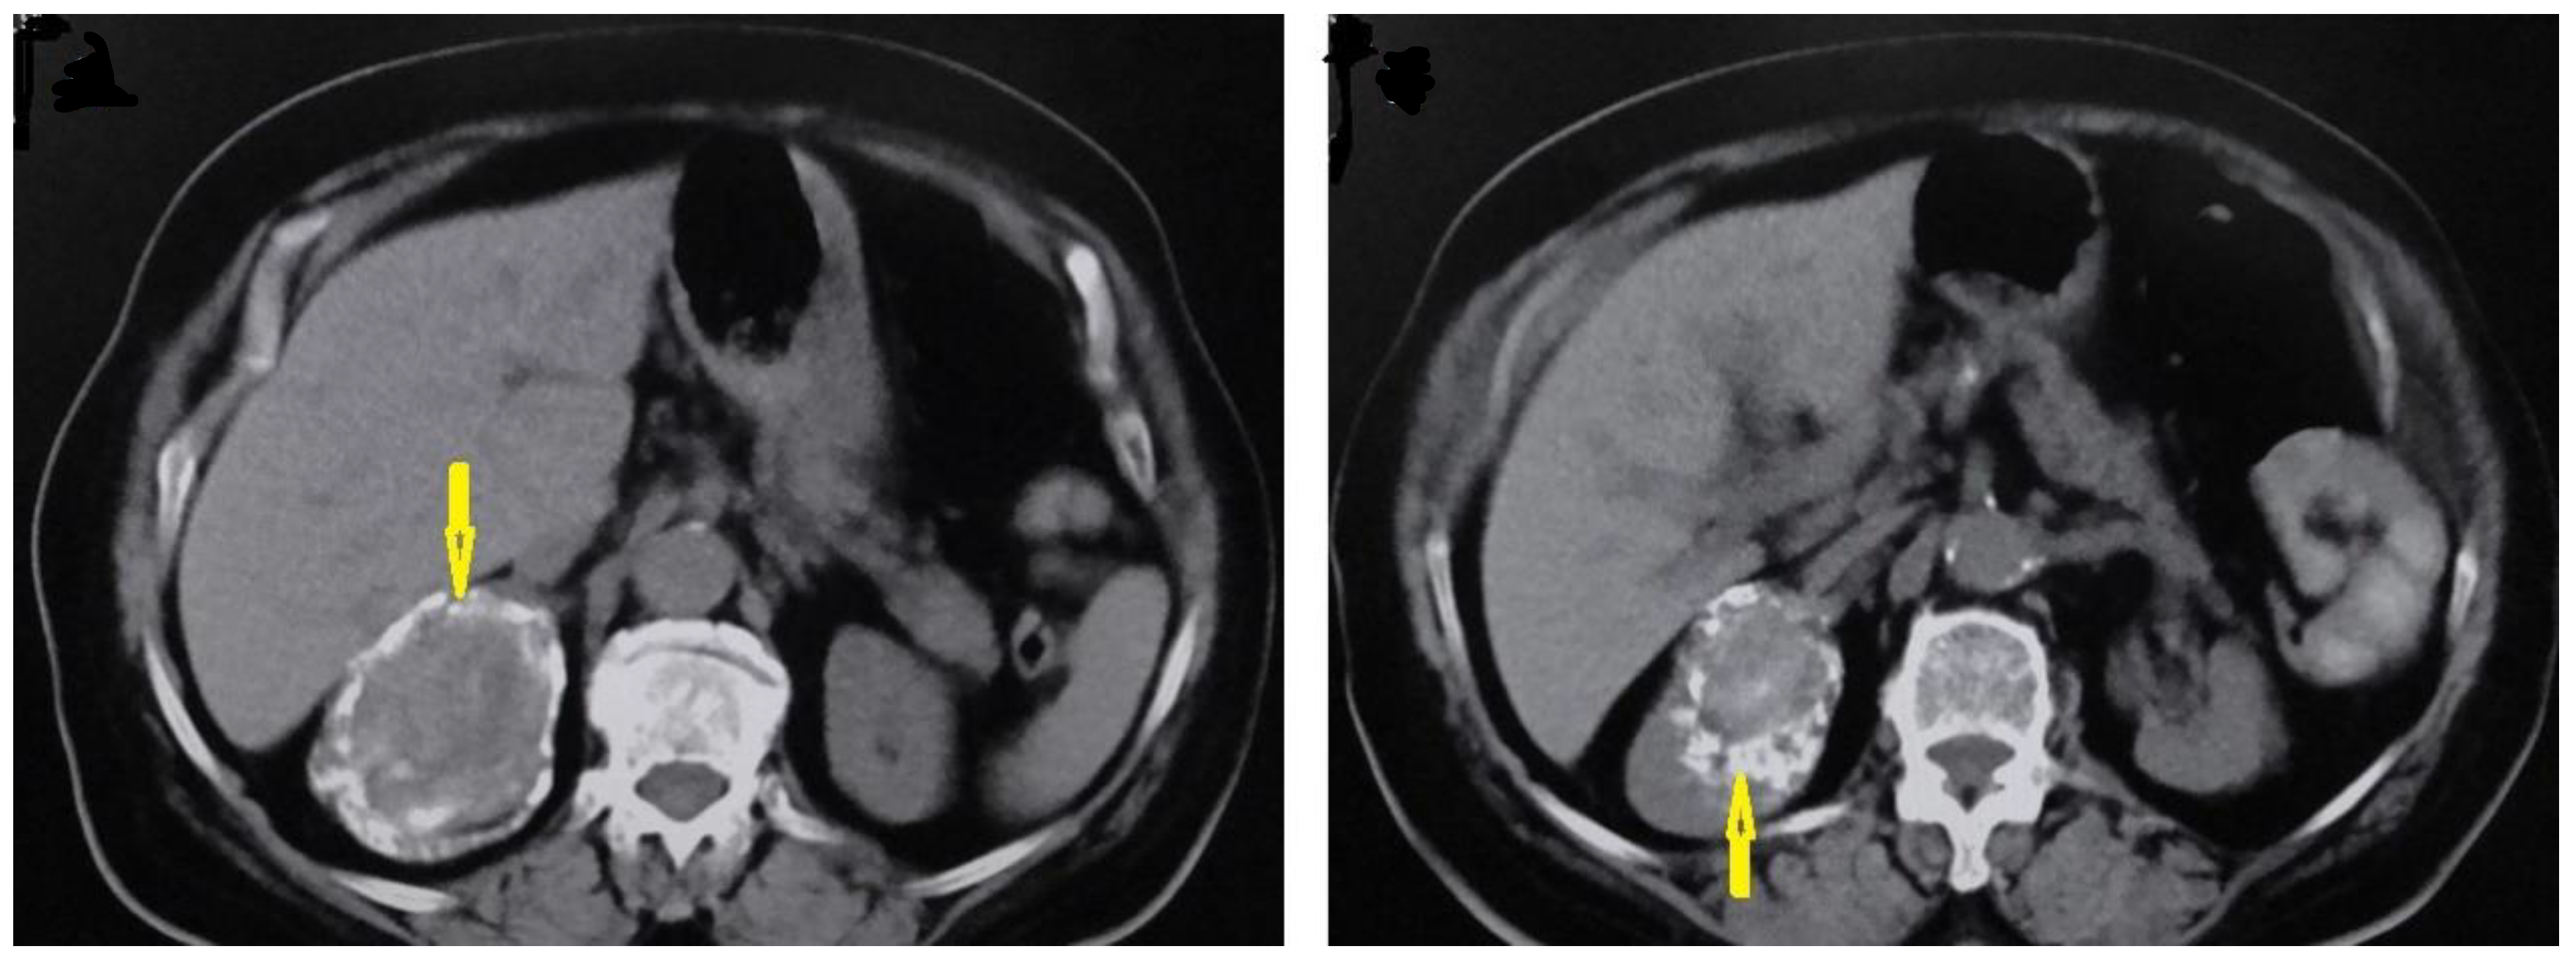

5.1. Hydatid Cysts of the Liver